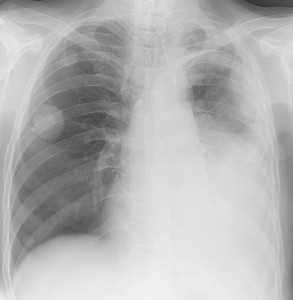

Как выглядят метастазы в легких на рентгене? Слева — узловые образования у пациента с раком яичка. Справа - метастазы рака яичников гематогенного характера с выраженным опухолевым лимфангиитом (обратите внимание на деформированный сетчатый, линейный характер легочного рисунка).